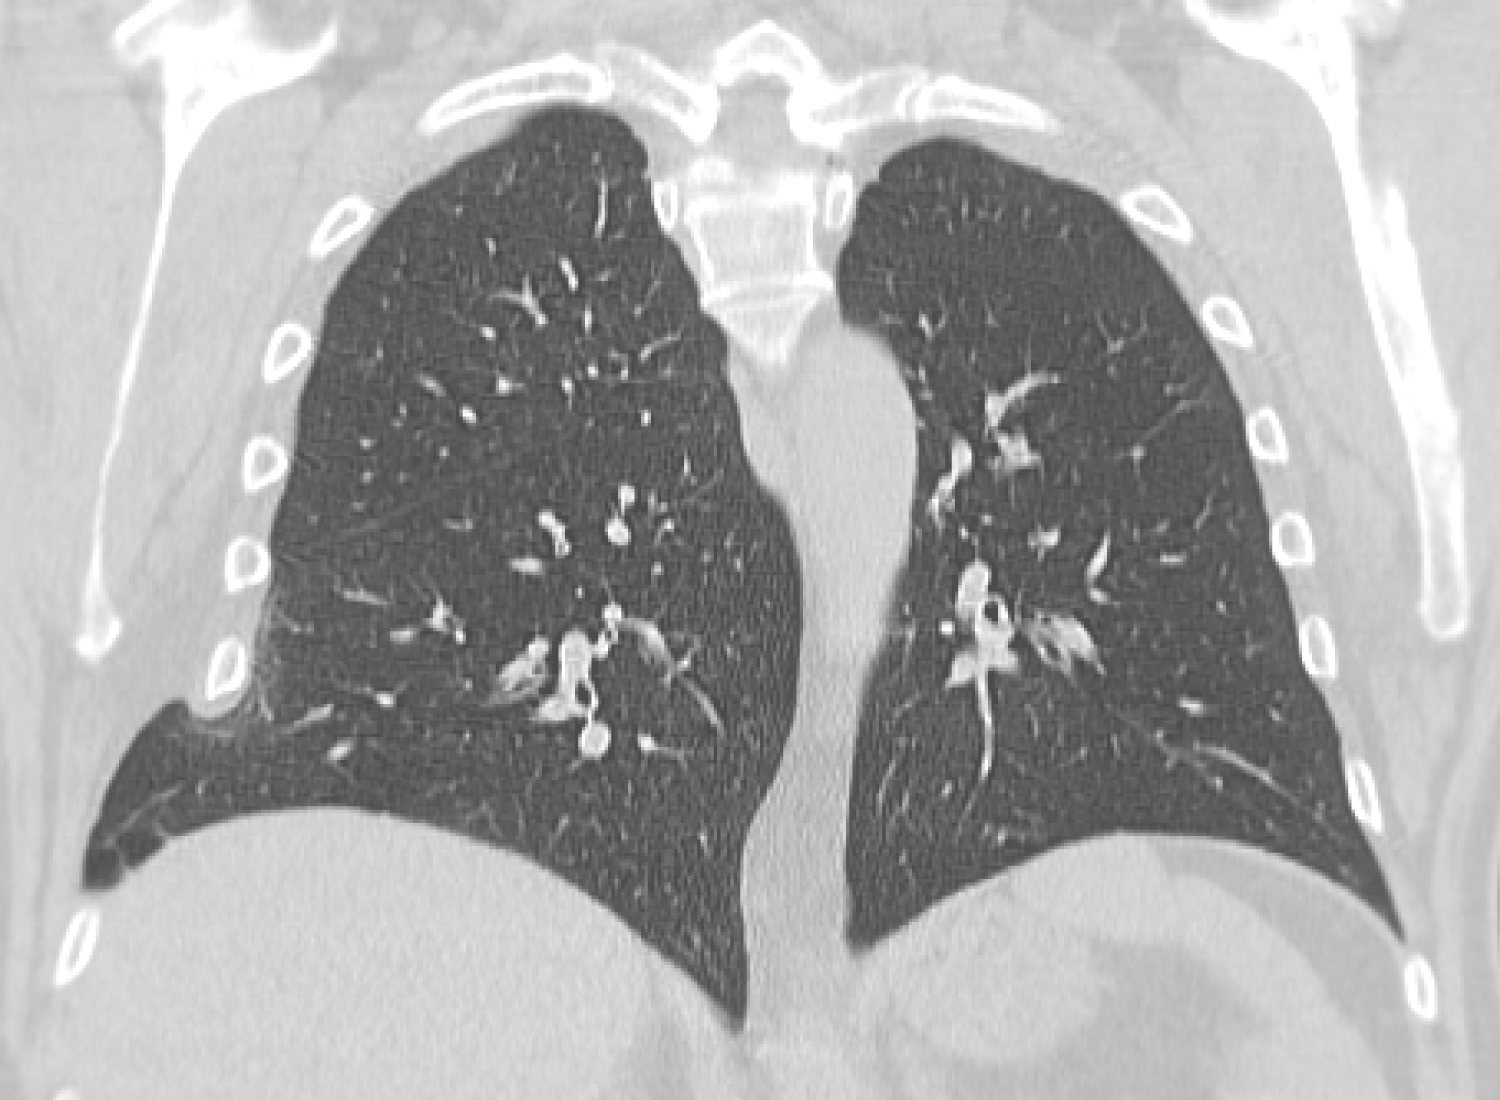

A 63 year old male with a history of smoking, COPD (GOLD I) and a diagnostic laparotomy for suspected small bowel pathology followed by multiple abdominal hernia repair operations of the lower abdomen, presented at the GP with chest pain during coughing spells. The coughing spells started several weeks ago. Though anamnesis revealed no prior trauma, a chest x-ray showed rib fractures of the 7th, 8th and 9th ribs on the right side, accompanied by herniation of lung tissue between ribs 7 and 8 (Figure 1a). A CT-scan of the chest confirmed the diagnosis of a lung herniation (Figure 1b). Vital signs were normal, however breathing was laboured with an increased respiratory rate. The patient was admitted to the Intensive Care Unit (ICU) for observation and pain management. He developed mild to moderate dyspnoea due to inadequate respiration, caused by pain for which an epidural catheter was placed. Because of further clinical decline the patient was planned for surgery. During the procedure a significant hernia sac covert by parietal pleura was found (Figure 1c). The rib cage was reconstructed using plates and vicryl sutures. Next, a polypropylene mesh was placed between the ribs for reinforcement (Figure 1d). There were no postoperative complications and in the next few days a full recovery followed. One year after surgery the patient was in good health and reported to have no discomfort during respiration or other physical discomfort.

Figure 1b: Computed tomogram frontal plane view shows herniation of lung tissue between ribs 7 and 8 on the right side. View Figure 1b